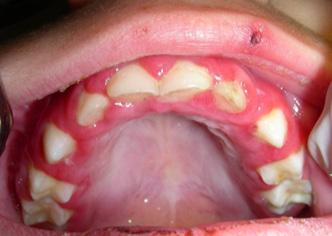

La mayoría de los casos ocurren en niños de 5 a 15 años, posterior a una faringitis bacteriana. Incidencia: 3 % en casos de una epidemia